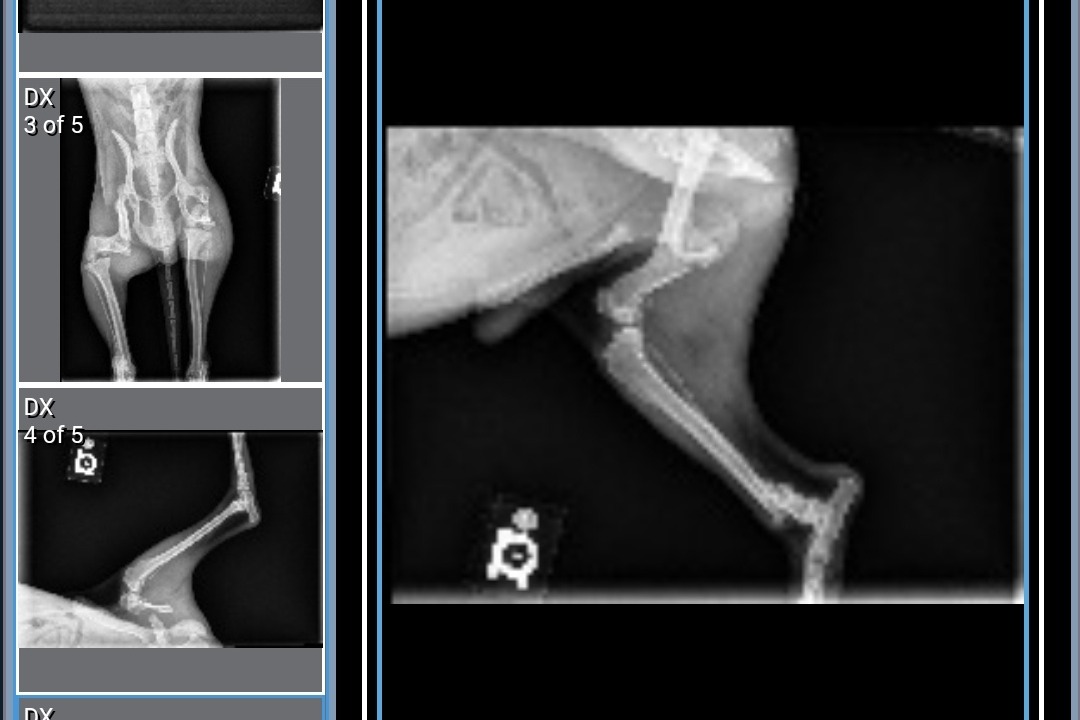

After x-rays, we found out that Mikko had two broken legs. One was an older fracture that had healed improperly and the other was more recent, his leg was completely detached and scraping against his muscle. Due to the fractures, Mikko suffered extensive muscle atrophy and has had to rely on his front legs for mobility. The doctors advised us to proceed with the surgery as soon as possible, stating, "There's still a chance to save his legs but if we wait, we will have to amputate."

The following images are Mikko's x-rays and the first documented photo of him when he was found.